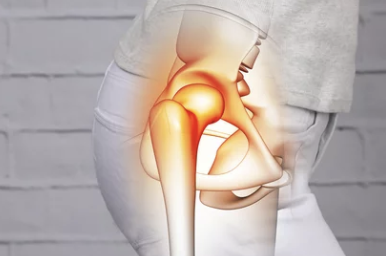

✅ 고관절 통증의 부위별 의심 질환

통증 위치 의심 질환

| 사타구니 안쪽 | 퇴행성 고관절염, 무혈성 괴사 |

| 엉덩이 바깥쪽 | 점액낭염, 대전자염 |

| 엉덩이 뒤쪽 | 요추디스크, 좌골신경통 |

| 허벅지와 골반 사이 | 고관절 충돌증후군, 인대염좌 |